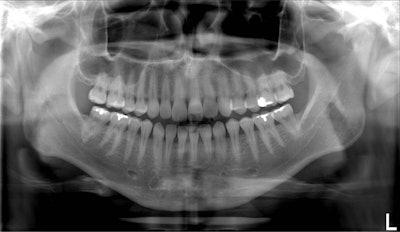

Standard panoramic image from a PC-1000 system using a CdTe sensor from Ajat, self-corrected with tomosynthesis software. Images courtesy of Dr. Robert Langlais.

Although the front teeth are distorted, the back teeth are no longer crossed. By manually positioning the patient in the system, the contacts are now open.